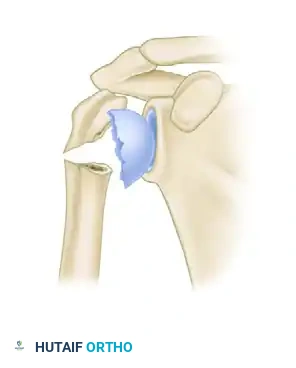

| كسر الثلاثة أجزاء | تنفصل ثلاثة أجزاء وتتحرك من مكانها، مما يسبب تشوهاً دورانياً في المفصل ويحتاج غالباً لتدخل جراحي. |

إليك بعض الصور الإشعاعية والرسوم التوضيحية الإضافية التي توضح أشكال التثبيت الجراحي المختلفة لكسور أعلى عظمة العضد